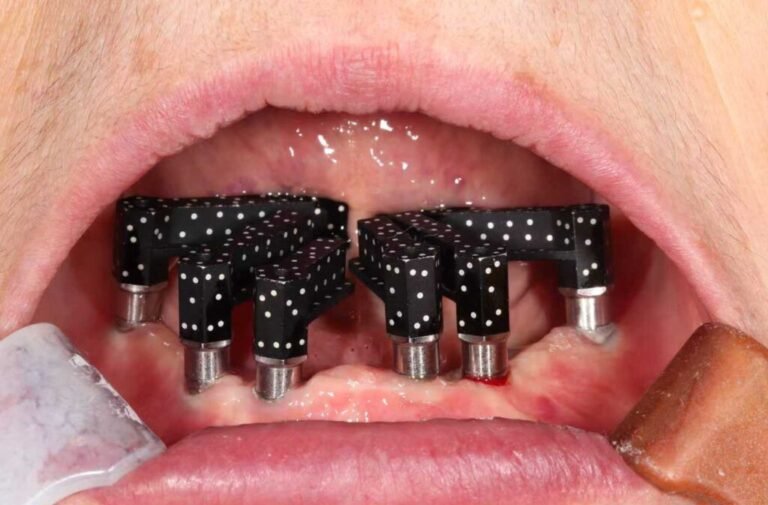

Photogrammétrie intra-orale en Implantologie

La combinaison du scan intra-oral et de la photogrammétrie (IPG) révolutionne l’implantologie en intégrant la précision de positionnement...